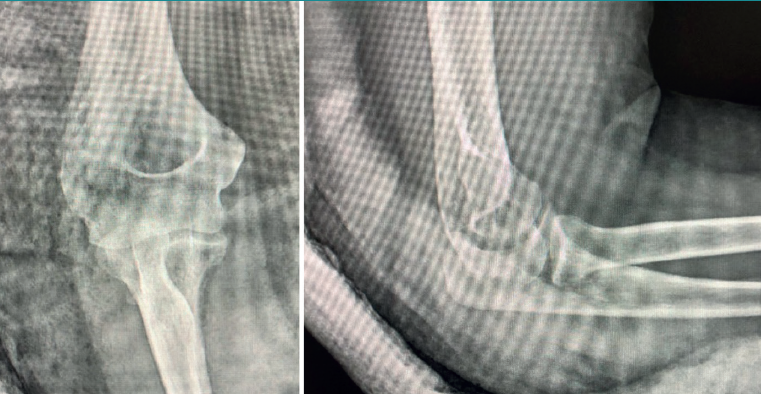

The patient was again evaluated in the clinic after 12 weeks. The physical examination revealed pain on the lateral aspect of the right elbow, with clicks on pronation, positive pivot shift manoeuvre and painful varus laxity. Complementary tests were requested: radiographs, which evidenced the Osborne-Cotterill lesion (Figure 1); a magnetic resonance imaging (MRI) scan showing distal deinsertion of the ulnar lateral collateral ligament and proximal deinsertion of the radial collateral ligament, as well as partial rupture of the annular ligament; and a computed tomography (CT) scan that found the Osborne-Cotterill osteochondral defect in the posterior capitellum to measure 8 × 3 mm (Figure 2). The patient suffered another posterior dislocation episode the following week after a new fall while undergoing rehabilitation. A second closed reduction was therefore performed.

In total, she experienced three further subluxation episodes in these weeks. In view of the great instability, surgical treatment was decided 6 months after the initial injury. The operation consisted of Docking type ligamentoplasty with an autologous graft from the gracilis muscle of the right knee and mosaicplasty measuring 8.5 mm in diameter with autologous grafting from the same knee.